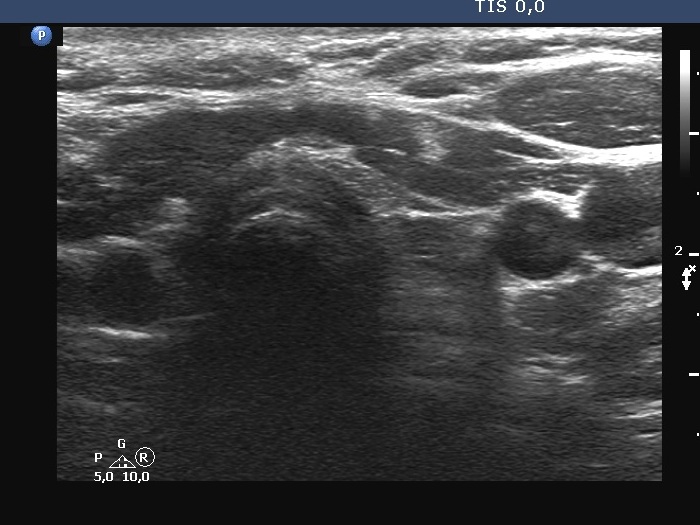

Second examination a year after surgery (third row of images):

Clinical presentation: The patient underwent on radioidodine therapy. She had no complaints.

Palpation: no abnormality.

Laboratory tests: TSH 0.04 mIU/L, FT4 22.2 pM/L on daily 150 microgram levothyroxine. Thyroglobulin was 1.09 ng/mL, anti-hTg was below 0.9 U/mL.

Ultrasonography. Both thyroid beds were filled with connective tissue. The left thyroid bed has a moderately hypoechoic area. Longitudinal section proved that this could not be a true nodule.